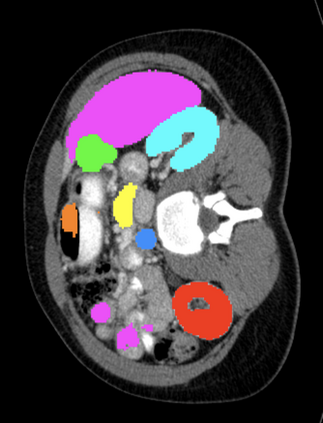

Most recent semantic segmentation methods adopt a U-Net framework with an encoder-decoder architecture. It is still challenging for U-Net with a simple skip connection scheme to model the global multi-scale context: 1) Not each skip connection setting is effective due to the issue of incompatible feature sets of encoder and decoder stage, even some skip connection negatively influence the segmentation performance; 2) The original U-Net is worse than the one without any skip connection on some datasets. Based on our findings, we propose a new segmentation framework, named UCTransNet (with a proposed CTrans module in U-Net), from the channel perspective with attention mechanism. Specifically, the CTrans module is an alternate of the U-Net skip connections, which consists of a sub-module to conduct the multi-scale Channel Cross fusion with Transformer (named CCT) and a sub-module Channel-wise Cross-Attention (named CCA) to guide the fused multi-scale channel-wise information to effectively connect to the decoder features for eliminating the ambiguity. Hence, the proposed connection consisting of the CCT and CCA is able to replace the original skip connection to solve the semantic gaps for an accurate automatic medical image segmentation. The experimental results suggest that our UCTransNet produces more precise segmentation performance and achieves consistent improvements over the state-of-the-art for semantic segmentation across different datasets and conventional architectures involving transformer or U-shaped framework. Code: https://github.com/McGregorWwww/UCTransNet.